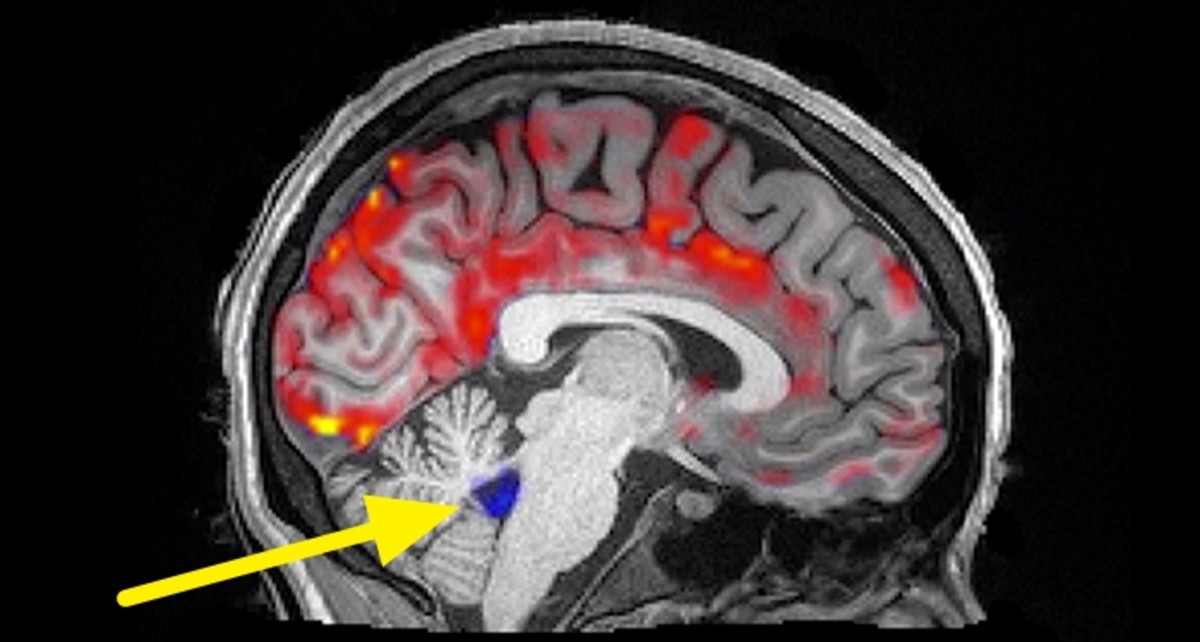

과거 미국 보스턴대 공대의 로라 루이스 생의학 공학 부교수 팀은 수면중인 뇌를 촬영한 자기공명영상을 하나 공개했다.

해당 영상에는 뇌척수액이 잠든 뇌를 구석구석을 깔끔하게 청소하는 장면이 고스란히 담겨있다.

영상에서 붉은색은 혈액의 움직임을 뜻한다. 혈액이 유입됐다 사라질 때 파란색으로 나타나는 부분이 뇌척수액의 유입이다.

혈류와 뇌척수액의 유입이 매우 리드미컬하게 번갈아 가며 박동을 이어가는 것을 볼 수 있다.

잠잘 때 신경세포의 활동이 조용해지면 혈액이 빠져나가고 대신 뇌척수액이 흘러들어오는데, 이 뇌척수액이 맥파의 리듬을 타고 뇌를 씻어낸다는 것이다.